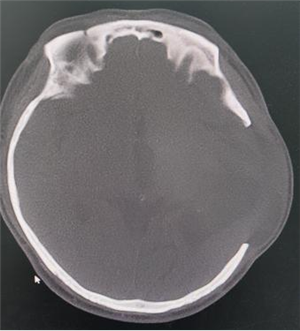

病例 1:一位 60 岁男性患者,因脑血管畸形脑出血接受开颅术后,出现颅骨缺损,我院采用自体颅骨修补。

术前